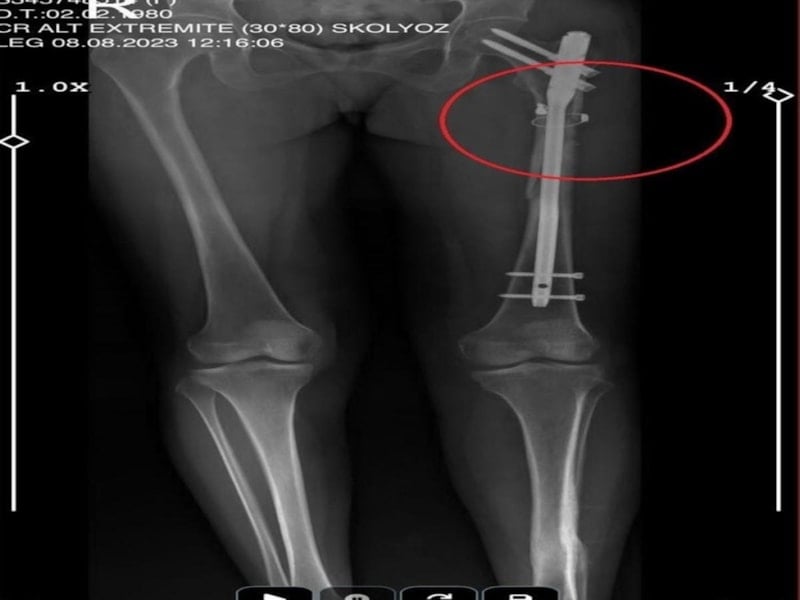

İlyas Sarıkaya, sevgilisi Fatma O.'yu da 8 kurşunla vurup, yaraladı. Arkadaşı Özaslan'ın cesedini önce çarşafa sonra da streç filme sarıp bantlayan Sarıkaya, eczaneden aldığı sargı bezi ve ilaçlarla pansumanını yaptığı sevgilisine yaralı haldeyken 21 gün boyunca cinsel saldırıda bulundu.

Eve giden ekipler, ağır yaralı haldeki Fatma O. ve kokmaya başlayan cesetle karşılaştı.